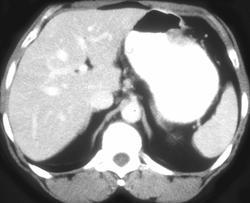

Gastric Leiomyoma